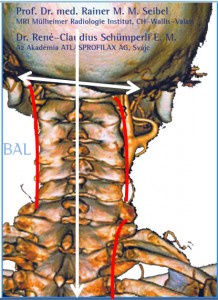

Súlyos testi és lelki panaszainak megoldását keresve René Claudius SCHÜMPERLI az 1993-1996-ig tartó intenzív kutatásai során rádöbbent arra, hogy a koponya-atlasz ízületben az Atlasz (első nyakcsigolya) szinte minden embernél ficamszerűen elfordult állapotban van. Megállapította azt is, hogy az atlasz elfordulását változó mértékű elbillenés is kíséri. Tehát a koponya alátámasztottsága nem vízszintes, és változó mértékű és súlyosságú egyensúlytalanság lép fel. A […]]]>

Súlyos testi és lelki panaszainak megoldását keresve René Claudius SCHÜMPERLI az 1993-1996-ig tartó intenzív kutatásai során rádöbbent arra, hogy a koponya-atlasz ízületben az Atlasz (első nyakcsigolya) szinte minden embernél ficamszerűen elfordult állapotban van. Megállapította azt is, hogy az atlasz elfordulását változó mértékű elbillenés is kíséri. Tehát a koponya alátámasztottsága nem vízszintes, és változó mértékű és súlyosságú egyensúlytalanság lép fel. A […]]]>

Elbillent Atlasz A Magyar AtlasPROfilax Társaság hivatalos honlapja és a specialisták megtekinthetők a http://atlaszprofilax.com honlapon. A világ 30 országában mintegy 350 specialista jogosult alkalmazni ezt a különleges eljárást, amit a svájci René Claudius SCHÜMPERLI dolgozott ki 1993-1996-ig. Az ATLASPROFILAX® egy speciális lágyrész wellness-masszázs kezelés, ami az első nyakcsigolya normális pozícióba való visszatérését teszi lehetővé. A feltaláló a világon elsőként észlelte […]]]>

Elbillent Atlasz A Magyar AtlasPROfilax Társaság hivatalos honlapja és a specialisták megtekinthetők a http://atlaszprofilax.com honlapon. A világ 30 országában mintegy 350 specialista jogosult alkalmazni ezt a különleges eljárást, amit a svájci René Claudius SCHÜMPERLI dolgozott ki 1993-1996-ig. Az ATLASPROFILAX® egy speciális lágyrész wellness-masszázs kezelés, ami az első nyakcsigolya normális pozícióba való visszatérését teszi lehetővé. A feltaláló a világon elsőként észlelte […]]]>